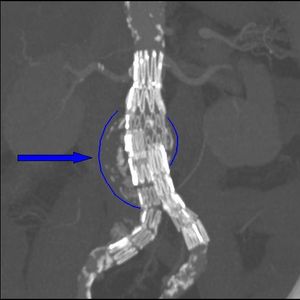

- 혈관내 치료 (EVAR): 1990년대에 처음 고안된 방법으로, 개복 수술의 대안으로 자리 잡고 있다. 스텐트와 인조혈관을 결합한 기구(스텐트그라프트)를 혈관 내에 삽입하여 늘어진 대동맥류 부위로 혈류가 직접 접촉하지 않게 한다.

일반적으로 나이가 많거나 개복 수술에 적합하지 않은 고위험 환자에게 적용되었으나, 점차 적용 범위가 확대되고 있다. 개복 수술보다 수술 사망률이 낮고, 통증이 적으며, 입원 기간이 짧고, 회복이 빠르다는 장점이 있다. 그러나 스텐트의 힘으로 인조혈관을 대동맥 벽에 밀착시키는 방식이므로, 밀착이 정확하지 않으면 혈류가 새어 대동맥류가 다시 커지거나, 대동맥 분지를 통해 혈류가 역류하여 대동맥이 계속 확장될 수 있다. 스텐트그라프트 자체의 손상 가능성도 있어 주기적인 검사가 필요하며, 장기간 경과 시 문제가 발생하는 경우가 보고되고 있다. 최신 연구에 따르면 EVAR 치료는 동맥류 관련 수술 사망률은 낮지만, 전반적인 생존율이나 건강 관련 삶의 질에는 개복 수술과 비교하여 큰 차이가 없을 수 있다.[142][143][144][145]